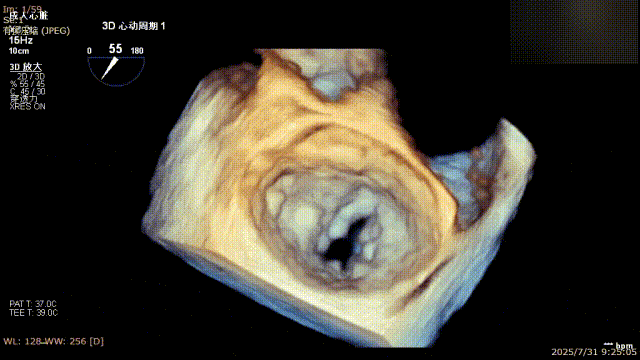

解离前三维

解离后三维